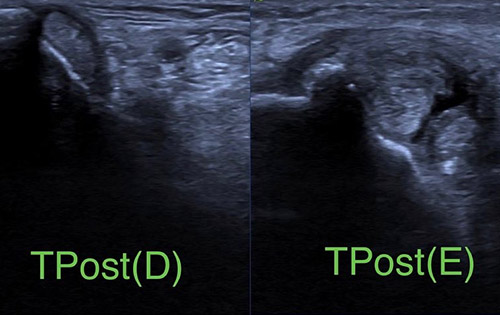

L’ecografia del peu és una prova diagnòstica que utilitza ultrasons d’alta freqüència per visualitzar les estructures del peu i del turmell, com tendons, lligaments, músculs i fàscia plantar. És una tècnica segura, ràpida i indolora.

L’ecografia musculoesquelètica permet diagnosticar moltes patologies del peu i del turmell, com ara fascitis plantar, lesions tendinoses, inflamacions, neuromes o lesions ligamentoses.

També és molt útil per fer seguiment de l’evolució de les lesions.